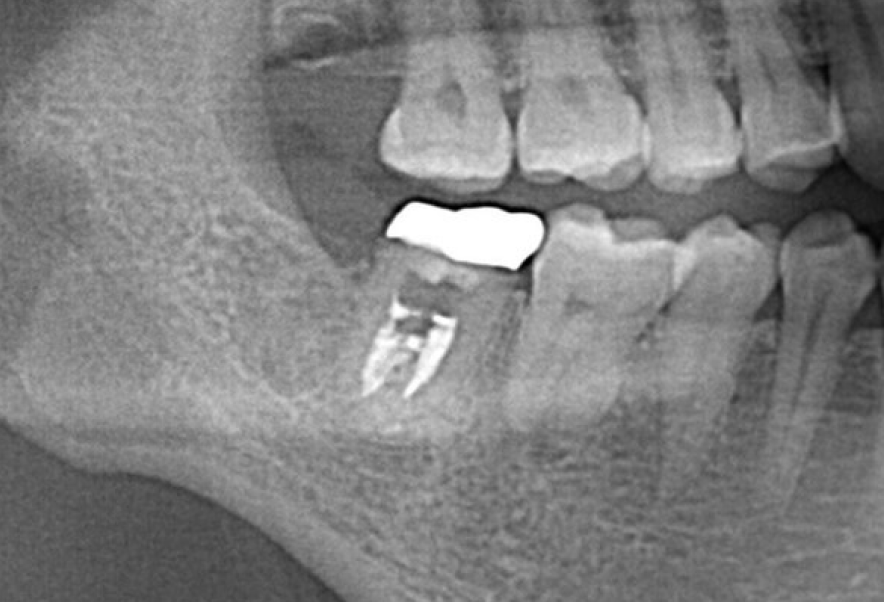

Before

After

他院で保険外根管治療・歯根端切除手術をしセラミックを装着後

すぐ膿んできた歯の再治療